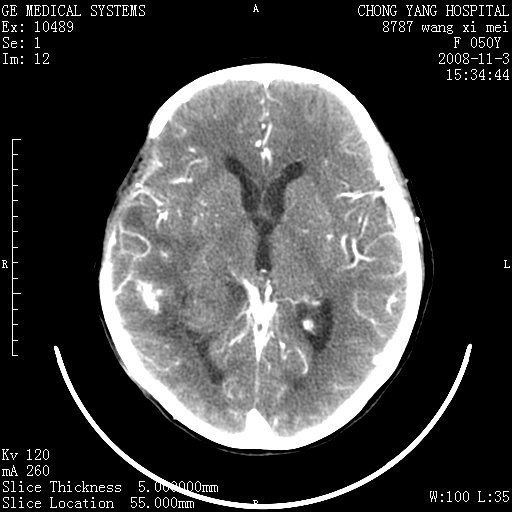

右侧颞顶部可见低密度实变影,内见不规则钙化灶,边界不清,占位效应明显,侧脑室后角受压移位,符合胶质瘤术后复发改变。

右颞骨局限性缺如,局部脑组织无外隆。右颞叶可见片状脑脊液样低密度影,边缘较清,右侧侧脑室三角区可见一块状等密度影,且伴有强化,余未见明显异常改变。

考虑:右大脑术后改变伴肿瘤复发。

手术后局部片状低密度改变(软化灶),其后方颞叶似等密度病灶,界限不清,内见钙化,有轻度占位效应,但增强后强化之血管走行如常。应不考虑:复发!

考虑右侧颞顶叶胶质瘤术后复发。

应考虑肿瘤复发,右颞顶叶已出现轻度强化肿块.必要时可与原片比较以下.

右侧颞顶部混杂密度影,内有钙化,有占位效应。应该是复发灶。结合术后片更好。

局部软化灶并钙化;无花边样强化,不象复发